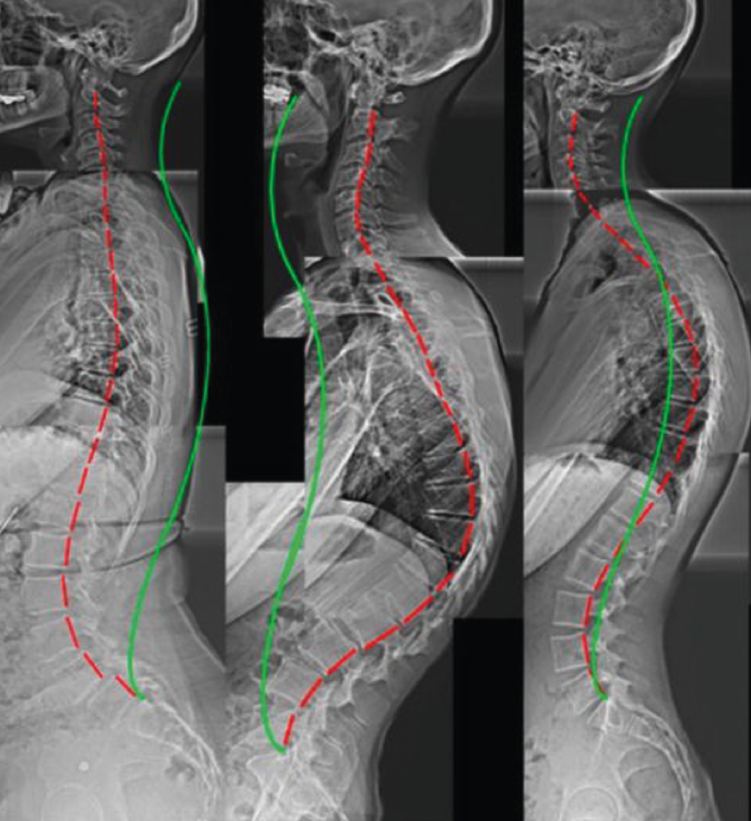

Otros hallazgos radiológicos frecuentes, como las anomalías congénitas de transición lumbosacra, espondilolistesis, secuelas de epifisitis, la espina bífida oculta, las escoliosis leves o moderadas, la hiperlordosis, espondiloartropatía, etc., se encuentran casi por igual en pacientes con y sin dolor lumbar (Figuras 5, 6 y 7)(22,23).

Figura 6. Secuelas de epifisitis. Reproducido de Perolat et al.(22).

Figura 7. Hiperlordosis. Reproducido de Oakley et al.(23).